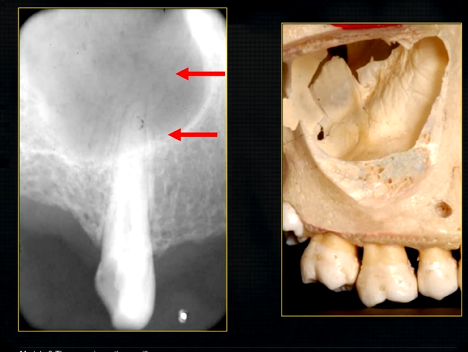

periapical radiograph → posterior maxilla

radiolucent maxillary sinus and radiopaque floor

radiopaque shadow cast by zygoma, hollowed out by maxillary sinus

lower end of the dense, zygomatic bone

posterior aspect of the maxilla - smooth round tuberosity

1st image taken using the bisected angle technique

2nd was taken using the geometrically accurate, paralleling technique

upper image is geometrically distorted

shadow caused by zygoma

this was taken using the bisected angle technique

x ray beam was directed below the zygoma

very lower of the zygoma is seen - projected above the apices

pterygoid hammulus - supports the muscles of the soft palate

coronoid process of the mandible